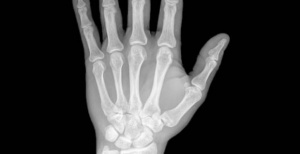

Bu hastalığın ilk belirtileri genellikle ellerde, ayaklarda ağrı ve acı hissi ve hareket kısıtlanmasıdır. 50 yaş üstü kişilerde çok daha yaygın olmasına rağmen, dizlerde, el ve ayak bileklerinde ağrı gibi semptomlardan şikayetçi olan gençler de vardır.

Eklem iltihabı eklemlerde ve dokularda iltihaplanmaya yol açarak normal dairesel hareketleri çok zorlaştırır. Bu bir öz bağışıklık hastalığıdır, yani organizmanın bağışıklık sistemi yanlışlıkla kendine saldırdığı zaman oluşur.

Bu hastalığa sahip olanların neredeyse tümü eklemlerinde yoğun ağrı hissederler ve bu ağrılar sabahları daha şiddetli olur. Ayrıca eklem sıcaklığı, kızarıklığı ve deformasyonu, ellerin ve ayakların uyuşması da sıklıkla karşılaştıkları sorunlardır.